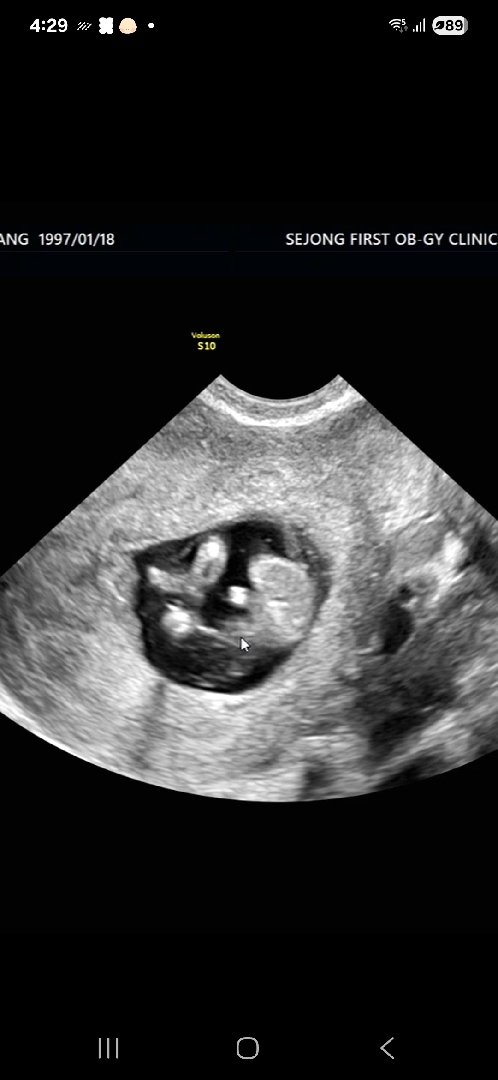

12주0일차 초음파..아들확정인가요??!

쌤은..다리사이를 잘보라며 뭐가있지 않냐는 말씀만 하셔서ㅜㅜㅋㅋ 아들인가요??!! 여쭤봐도 딱 보면 보일텐데 말씀만 하시네용.. 아들같기는 한데 아들확정인가효..?? 혹시 12주차에 이정도 촘파였는데 딸로 반전있으셨던분 있으실까요..??🥹🥹

12주차면 정확하지 않는데요 16주되야 정확해요

아들같아요